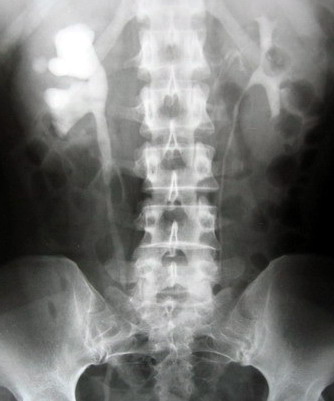

该手术对于输尿管中下段结石可在发病后快速进行腔内碎石,不用开刀,经尿道碎石,无需特殊术前准备,患者发病后可立即进行手术,直接将结石击碎取出,甚至术后无需留置导尿管和输尿管支架管,这样避免了腰椎穿刺引起的腰痛及头痛等腰麻的并发症。术前、术后都无需禁食,对合并糖尿病的患者更好管理。术后无管化也避免了插管给病人带来的疼痛不适。住院时间明显缩短,一般术后48小时可出院,整个住院费用减少1/3—1/2。手术效果可谓立竿见影,立即解除痛苦,该技术处于全国领先水平。针对输尿管中下段结石,可作为一种常规手术方式进行全面推广。同时,潍坊市市立医院泌尿外科目前还拥有全国最先进的体外冲击波碎石机,德国进口输尿管镜、经皮肾镜,瑞士进口EMS气压弹道碎石机。欢迎广大病友咨询。